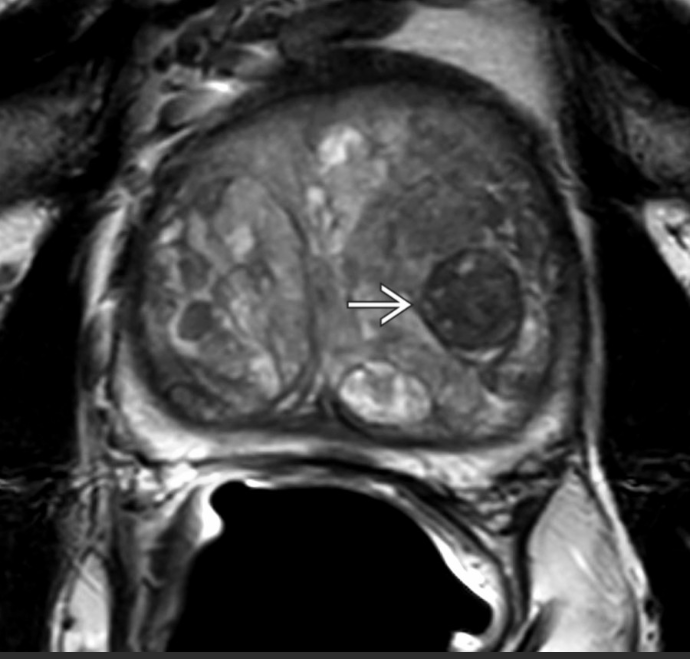

PI-RADS 5.

ADC axial mostra sinal marcadamente diminuído (esquerda). A imagem correspondente em DWI mostra sinal marcadamente aumentado. Escore PI-RADS DWI foi 5. Escore PI-RADS global é 5. Biópsia revelou câncer com Gleason 4+3 (grupo de grau 3).